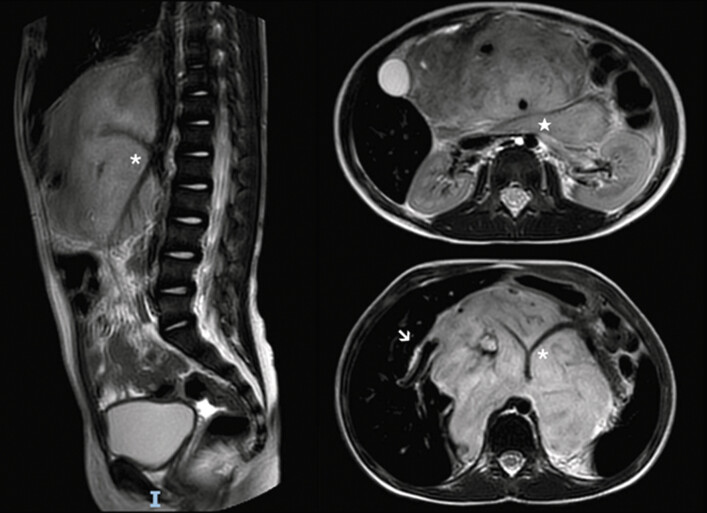

After completing treatment, at the age of 7, she underwent laparotomic tumor excision at our institute. Preoperative magnetic resonance imaging (MRI) revealed several image-defined risk factors, including tumor infiltration of the porta hepatis, encasement of the celiac axis and superior mesenteric artery origins, and involvement of the duodenopancreatic region ( Fig. 1 ). During dissection, an incidental CBD injury occurred, which was repaired with end-to-end anastomosis and biliary drainage. Due to the tumor’s complexity, only a partial resection was achieved, leaving significant macroscopic residual disease. Pathology revealed a predominance of Schwannian stroma (75%) with 25% neuroblastic cells, of which 85% were viable tumor and 15% showed postchemotherapy necrosis.